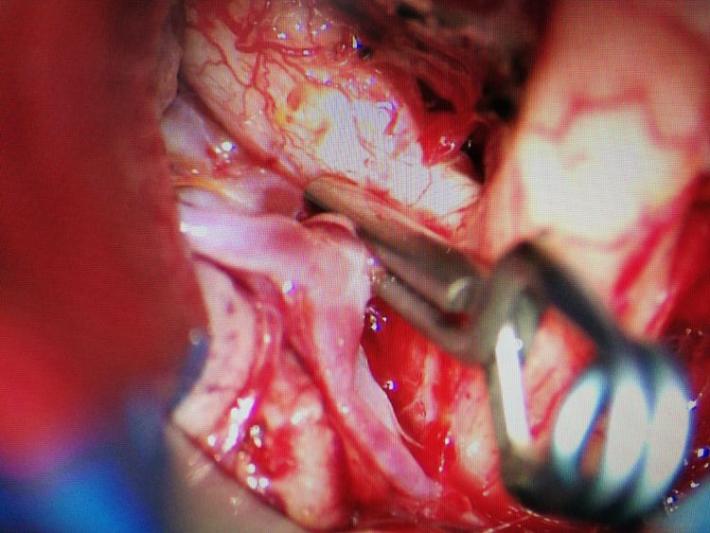

右侧翼点入路,解剖脑池系统,见前交通动脉瘤向右前伸入右侧视神经下方。予以夹闭。

显露诸血管正常。